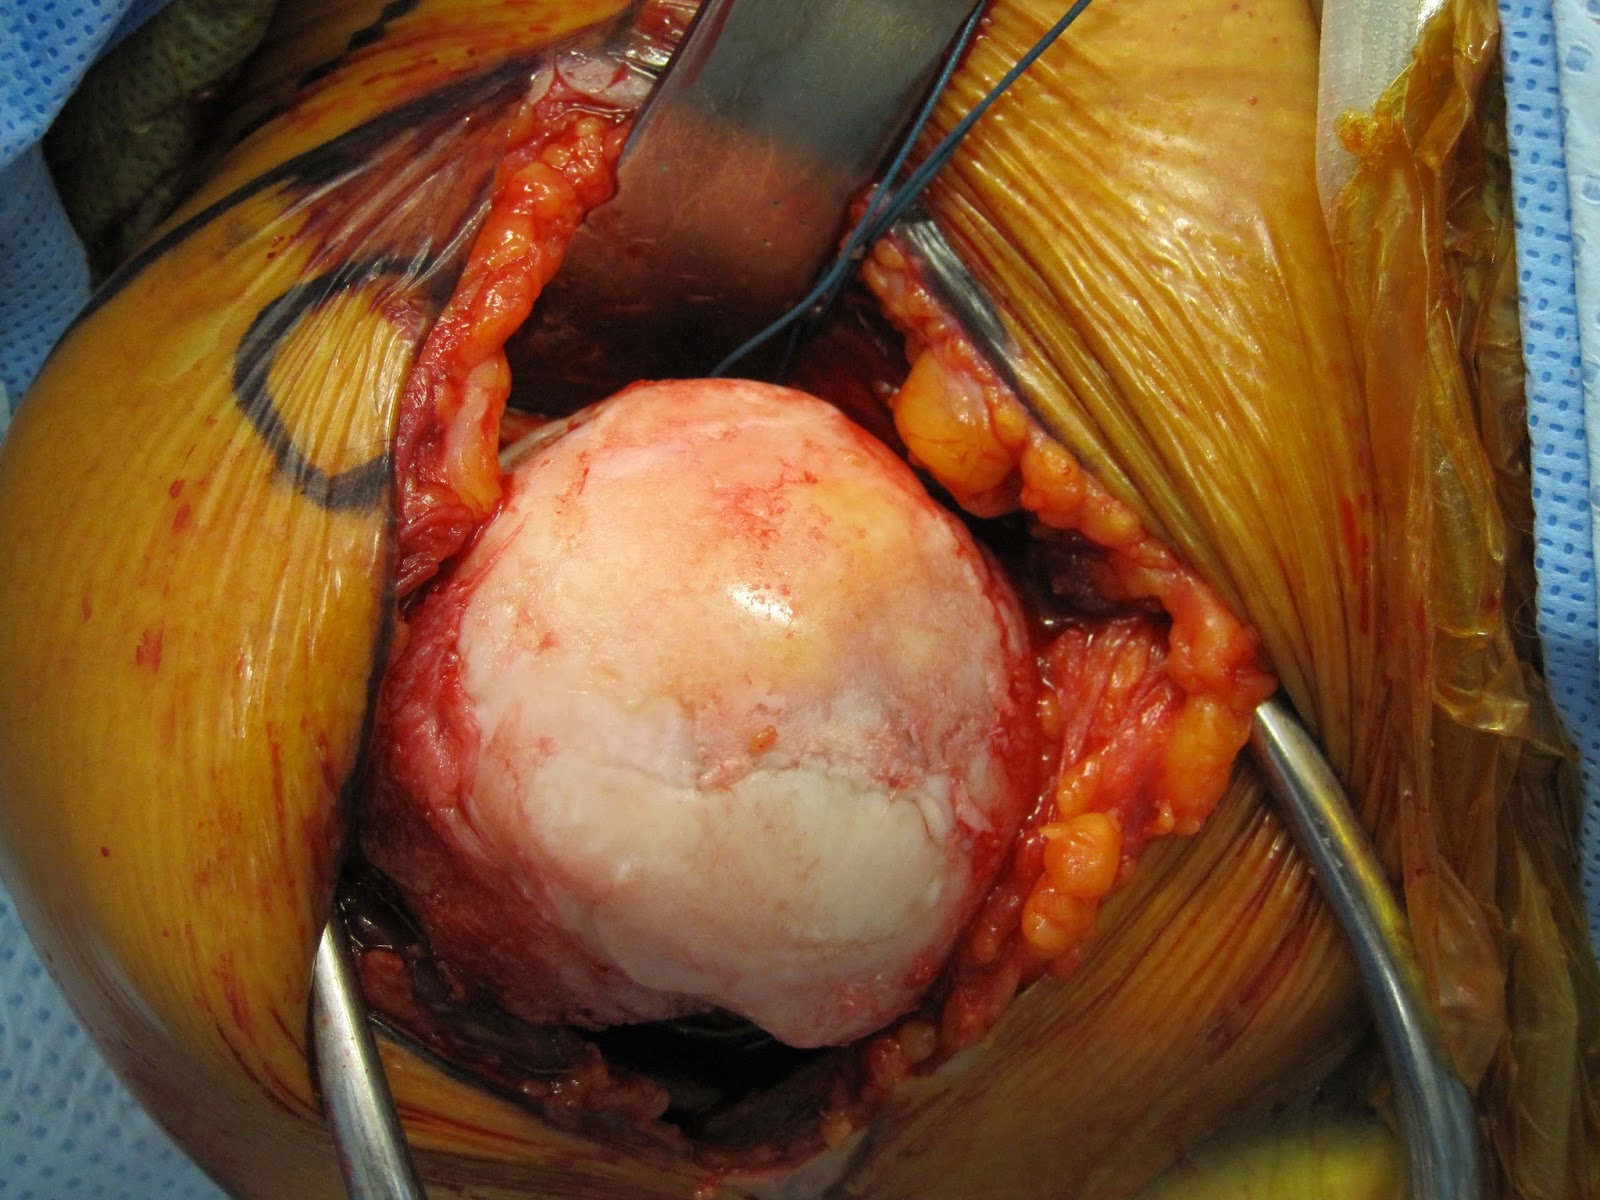

At surgery, the loss of cartilage over the humeral head was evident.